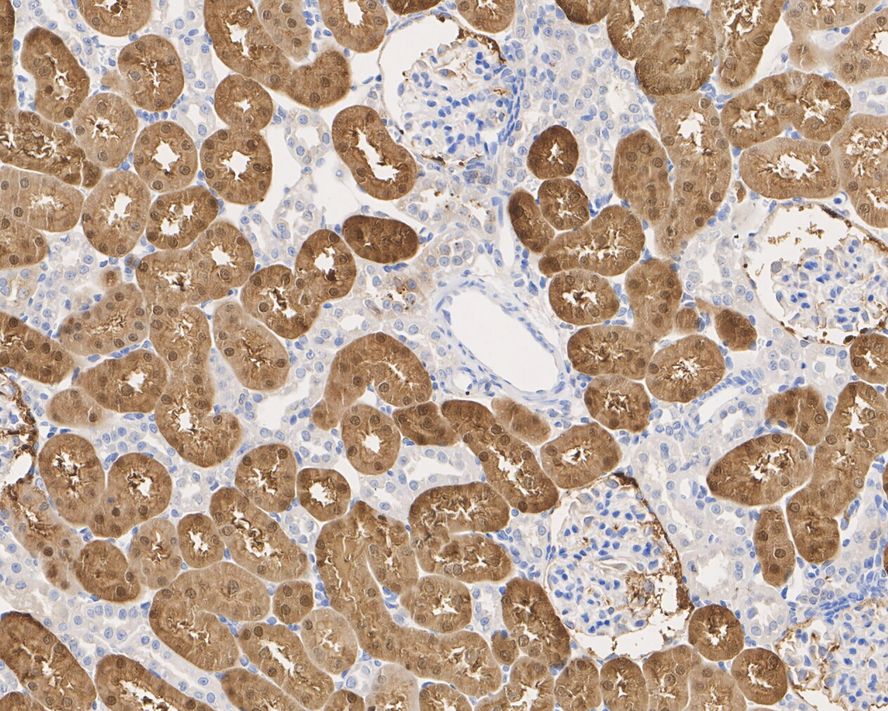

Immunohistochemical analysis of paraffin-embedded human kidney tissue with Mouse anti-ACY1 antibody (EM1901-86) at 1/2,000 dilution.

The section was pre-treated using heat mediated antigen retrieval with Tris-EDTA buffer (pH 9.0) for 20 minutes. The tissues were blocked in 1% BSA for 20 minutes at room temperature, washed with ddH2O and PBS, and then probed with the primary antibody (EM1901-86) at 1/2,000 dilution for 1 hour at room temperature. The detection was performed using an HRP conjugated compact polymer system. DAB was used as the chromogen. Tissues were counterstained with hematoxylin and mounted with DPX.